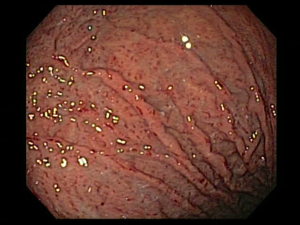

Detección endoscópica de las condiciones precancerosas

El uso de la endoscopia de luz blanca de alta resolución con una cromoendoscopia es de mucha utilidad y mucho mejor teniendo una precisión diagnóstica del 88% y una especificidad del 94% y una sensibilidad del 74,6% siendo esta la más utilizada, la toma de biopsias según sydney tenían precisiones diagnósticas de atrofia y metaplacia en un 93 y 90%, entonces esto sería de mucha utilidad para un diagnóstico precanceroso.